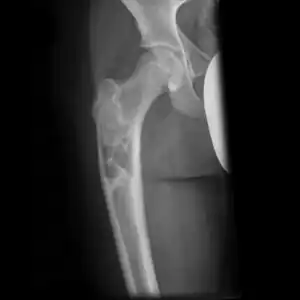

X-ray: Simple bone cyst in left upper arm of 13 year old

Simple bone cysts are often found incidentally on X-rays. About 90 to 95% of the lesion is found in metaphysics of long bones. The cyst is centered, oblong in shape along the long axis of a long bone. Rarely, they are large and multicameral and are found in diaphysis. When fracture is present, there may be a small bone fragment migrated in the cystic fluid. This is called "fallen fragment sign" which is diagnostic of simple bone cyst. Besides, a bubble migrating upwards (known as "rising bubble sign") is another feature suggesting of simple bone cyst.[7]